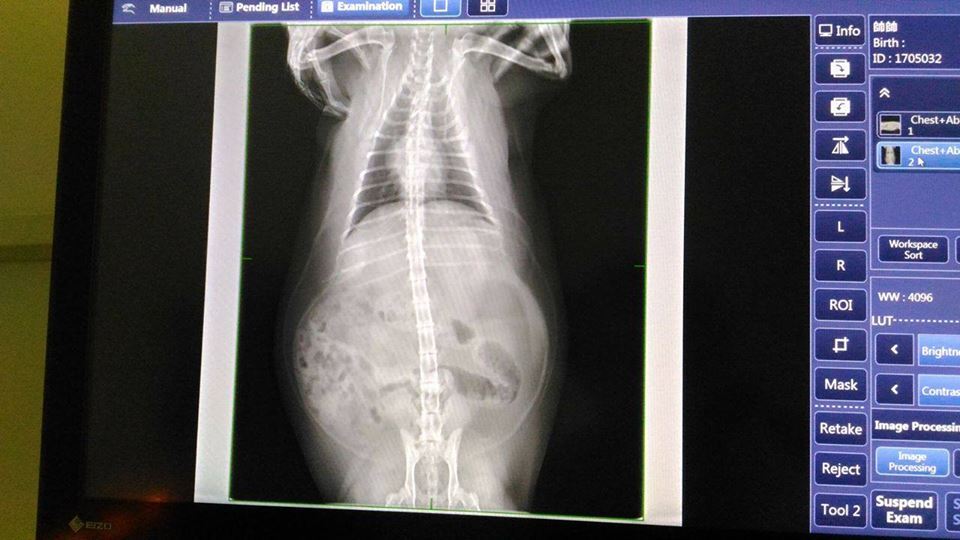

5/18 澄諾初診 帥帥9.7KG 38.9℃

【初診狀況】

因為帥帥蛀牙,不怎吃東西,今日就醫。

下排右後方牙齒已經爛掉,拔牙的日期,跟醫生會再討論。

順便做血檢,X光檢查。

血檢狀況都還不錯沒異狀,X光看起來白白的都是油脂...